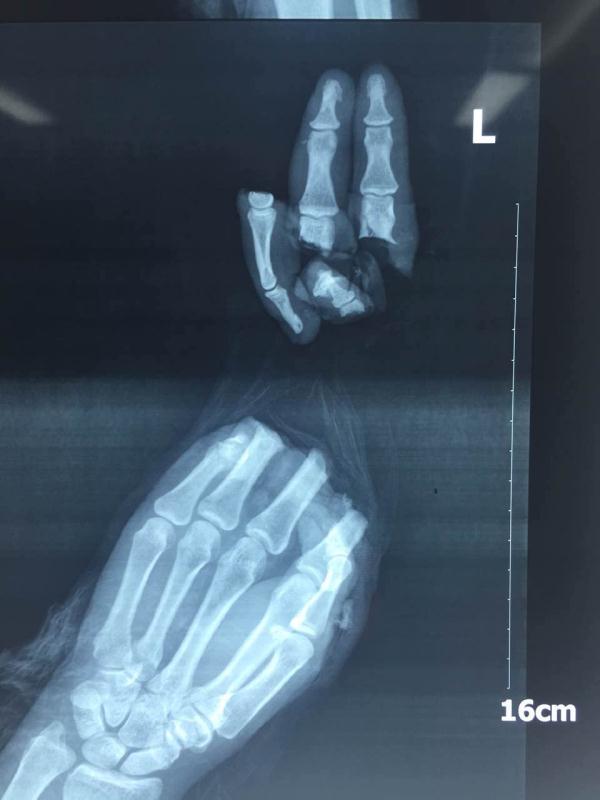

患者的左右手X光片:9指被切断,情势危急